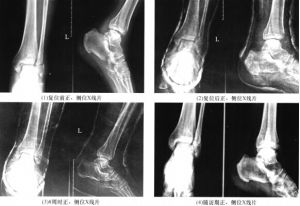

三踝骨折內踝是脛骨遠端的,外踝為腓骨遠端。後踝又叫後唇,是脛骨和距骨關節面的後緣。

對踝關節非開放傷有明顯脛距關節脫位者,術前必須儘早行手法復位;開放傷者予徹底清創。先取內踝後內側弧形切口,暴露內後踝骨折處,注意顯露後踝時切開脛後肌鞘向後推開,勿損傷脛後血管及脛神經。將內後踝復位,克氏針臨時固定,然後用拉力螺釘固定。如脛骨關節面出現塌陷,必須恢復關節面平整,必要時並行松質骨植骨。外踝取外側切口,顯露腓骨及下脛腓聯合處,腓骨復位後行鋼板螺絲釘內固定,合併下脛腓分離則必須恢復下脛腓聯合解剖關係,在踝關節面上方2~3cm處用4.5mm拉力螺釘平行踝關節面貫穿脛腓骨固定。檢查折端穩定性,沖洗切口及踝穴,兩切口分層縫合。內踝放置膠片引流,36h後拔除。術後常規用抗生素5~7d,術後2~3d開始主動踝關節屈伸鍛鍊,至X線複查骨折線模糊始漸行負重行走。術後維持小腿功能位石膏托外固定2周。